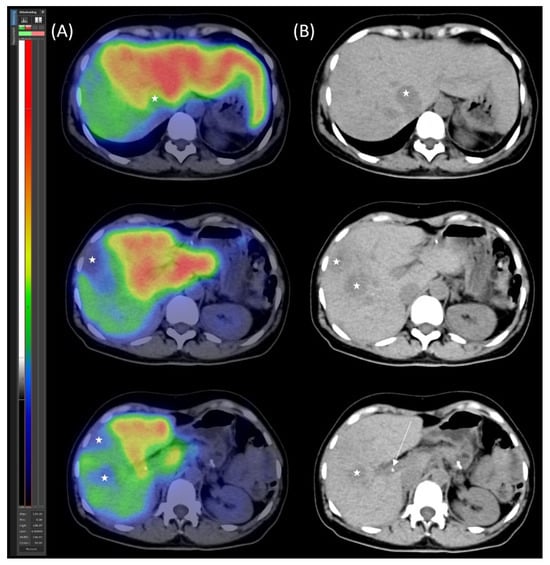

Control segmental liver function was assessed using [99mTc]Tc-mebrofenin SPECT/CT (Figure 4). The imaging confirmed adequate hypertrophy of the future liver remnant (FLR), with the following values: FLR volume fraction (FLR-V%) at 46%, FLR functional volume fraction (FLR-FV%) at 66%, and FLR filtration rate at 3.16%/min/m2.

Figure 4. [99mTc]Tc-mebrofenin SPECT/CT after parenchymal modulation. (A) Transaxial SPECT/CT and (B) native low-dose CT images show the distribution of functional hepatocytes, highlighting the dominance of the hypertrophied left lobe. The right lobe metastases appear as photopenic hypodense areas (marked with stars), with the arrow indicating the right portal vein ligation.